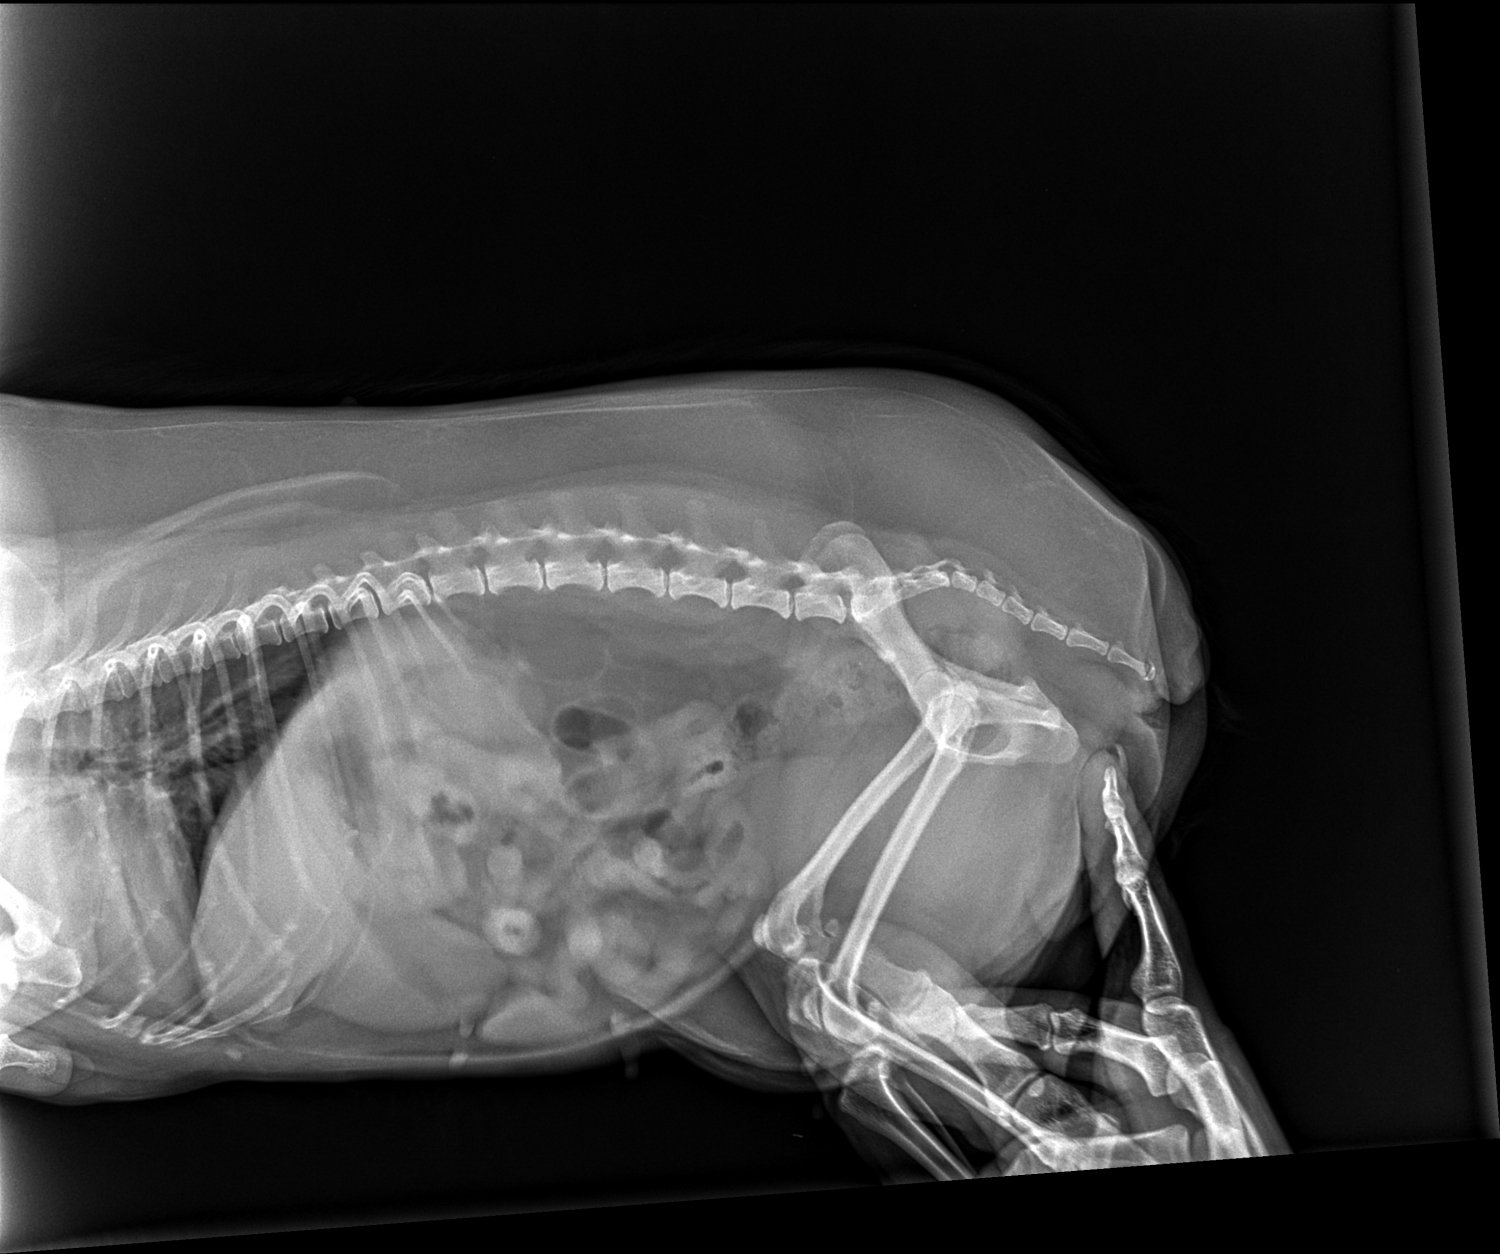

Zawsze to ja pomagam innym, ale tym razem zmuszona jestem o tą pomoc prosić. Moja ukochana psia córeczka od pewnego czasu ma ataki, które objawiają się zesztywnieniem całego ciała lub ograniczoną ruchowością i dużą trudnością w poruszaniu się. Weterynarz podejrzewał najpierw, że jest to na tle neurologicznym, została przebadana, lecz nie stwierdzono żadnych nieprawidłowości. Podejrzewał, że jest to na tle nerwowym, więc brała leki uspokajające, odstesowujace. W między czasie powtórnie wielokrotnie badana, ze względu na dalsze ataki. Badania wychodziły dobrze. W niedzielę 22 sierpnia od ok. godz. 14:00 do 22:00 (do póki nie zasnela) miała problem z poruszaniem się, każdy krok sprawiał jej trudność. W poniedziałek znów udałam się do weterynarza i pojawiły się podejrzenia, że jest to jednak na tle ortopedycznym. Dziś trafiłam do świetnego ortopedy, który wykonał szereg badań, w tym RTG - zdjęcia i opis załączone. Okazuje się, że jest duży problem zwyrodnienia. Otrzymała leki i konieczne jest wykonanie MRI oraz prawdopodobnie operacja. Nieststy to wszystko wykracza poza moje możliwości finansowe, dlatego bardzo chciała bym prosić Państwa o wsparcie. Ona jest dla mnie jak córka, bez niej nie wyobrażam sobie życia i zrobię wszystko, aby była zdrowa. Będę ogromnie wdzięczna za każdą złotówkę przekazaną na jej leczenie. Osobą zainteresowanym mogę przesłać filmiki, na których widać jak duży jest to problem i jak bardzo potrzebna jest jej pomoc.